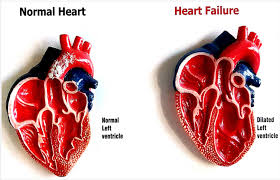

Cardiac Electrophysiologist with expertise in the field of cardiac arrhythmias. Areas of specialisation include pacemaker and heart failure device (CRT / defibrillator) implantations, electrophysiological studies, and radiofrequency ablation.